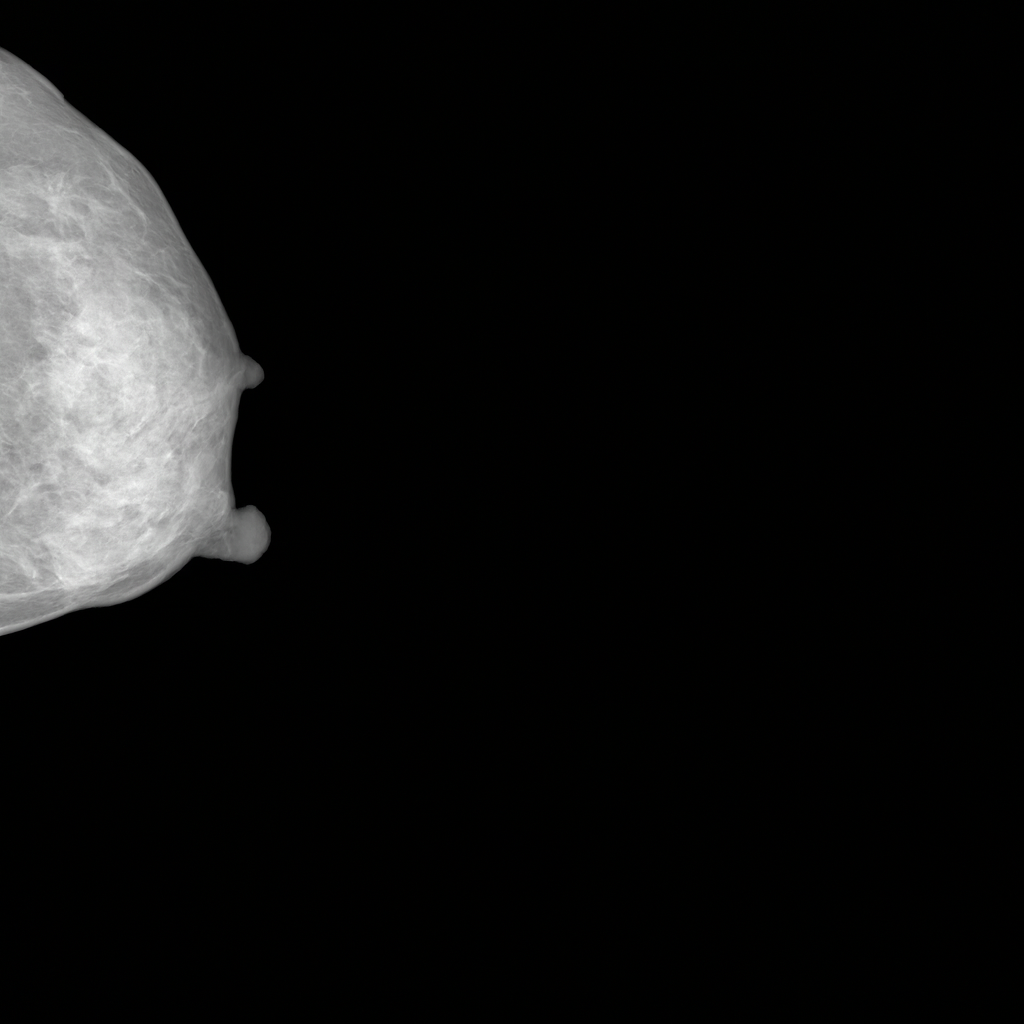

To evaluate MAMBO’s controllability, the model was trained with conditioning on BI-RADS categories on RSNA data and assessed by expert radiologists. The study shows that MAMBO can generate realistic breast images representing both normal and pathological cases. Radiologists were able to identify key clinical findings, including masses and calcifications, and assign different BI-RADS categories. Upon expert evaluation, 22.9% of synthetic images were labeled suspicious (BI-RADS 4 and 5), aligning with the original distribution presence of these anomalies, 28.6%. This alignment suggests that MAMBO is not only capable of generating realistic lesions but also exhibits controllability over pathological content.

17 Examples of Lesions on Images Generated by MAMBO Annotated by Experts

Realistically generated clinically relevant features (such as masses and calcifications) spotted and annotated by expert radiologists are shown on Fig. 15.